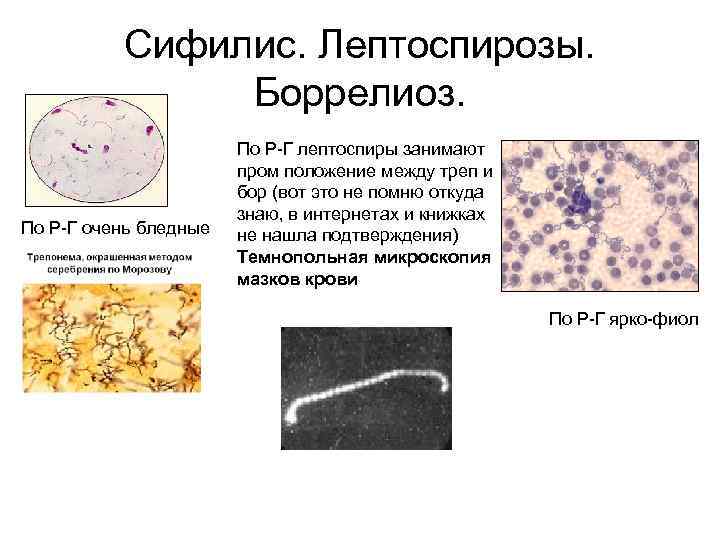

Лептоспиры: фотографии удивительных микроорганизмов